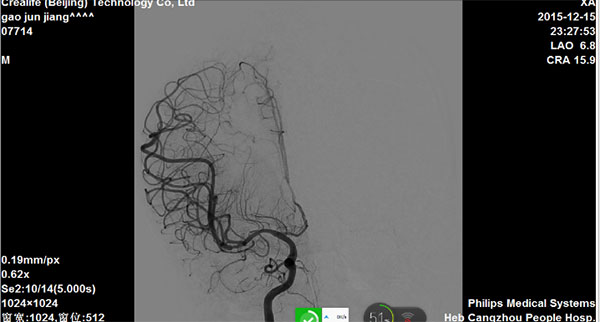

造影评估:急性左侧大脑中动脉闭塞

图1

图2